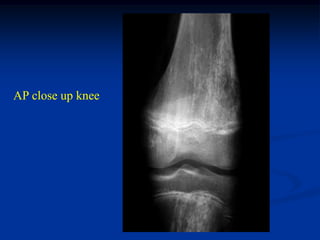

Case #572

15 year female

Ollier’s disease

AP close up knee